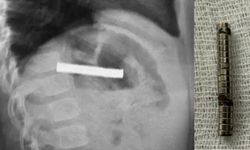

Denetimlerde en çok dikkat çeken uygunsuzluklar et ve et ürünlerinde görüldü. Bazı numunelerde domuz eti, tek tırnaklı eti ve sakatat tespit edildi. Ürün etiketlerinde yer almayan deri dokusu ve kanatlı eti gibi içeriklere de rastlandı. Bu durum sağlığı tehdit eden önemli bir gıda güvenliği sorunu olarak değerlendirildi.